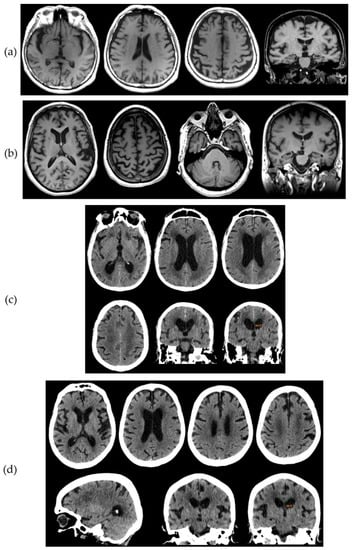

Figure 2. (a) T1 Magnetic Resonance Imaging (MRI) sequences of patient 1. Frontal (mainly), frontoparietal, perisylvian, and left hippocampal (grade 3) atrophy is observed. (b) T1 MRI sequences of patient 2. Atrophy in the left posterior perisylvian and parietal area is observed with preservation of the hippocampus. (c) Computerized tomography (CT) scan of patient 3. Some degree of frontal and parietal atrophy is seen. The white matter shows decreased density consistent with subcortical small vessel disease, in addition to periventricular caps. The parietal convexity is tight, the callosal angle is 84.4° and the Evans index has been calculated to 0.36. (d) CT scan of patient 4. Frontal (mainly) and parietal asymmetric atrophy are observed. Although the parietal convexity is not tight, the callosal angle is 88.4° and the Evans index has been calculated to 0.38. Decreased density of the white matter at centrum semiovale is noted, consistent with small vessel disease, with additional periventricular caps.

A seventy-six-year-old female was examined due to four years of “memory problems”. She increasingly had to keep memos and frequently repeated the same questions. According to the results of the neuropsychological testing, she had incipient dementia, with a profile more compatible with a frontal or frontal-subcortical syndrome (decreased attention and concentration and executive function) rather than the typical hippocampal amnestic syndrome (Table 1). Neuroimaging showed frontal–frontoparietal atrophy and asymmetric hippocampal atrophy (Figure 2a). Biomarker assessment showed decreased Aβ42 and Aβ42/Aβ40 ratio and increased both τP-181 and τT, compatible with AD.

This seventy-six-year-old female suffered gradually progressive difficulty in speech for three years. Upon examination, she had a perfect understanding of language, but during spontaneous speech she made many pauses in an effort to “recall” the appropriate word. Upon naming testing, anomic (word-finding) difficulty was obvious, with object knowledge and single-word comprehension completely spared. Phonological errors were frequent and sentence repetition was severely affected. The motor and grammatical aspects of speech were normal. No difficulty in other cognitive domains was reported and decreased scores in neuropsychological testing were attributed mainly to the language (aphasic) disorder. She had no other significant difficulty in activities of daily living except in communication due to the aphasic disorder, which was compatible with Primary Progressive Aphasia (PPA) of the logopenic-type [49]. Atrophy was predominant in the left perisylvian and parietal areas (Figure 2b). Biomarker analysis revealed normal Aβ42 with reduced Aβ42/Aβ40 ratio, together with increased τP-181 and τT, compatible with AD.

An eighty-one-year-old male developed a gradually progressive cognitive decline during the last four years. He had apathy, social withdrawal difficulty in performing complex tasks, mental “slowness”, and reduced attention. The previous year, progressive gait difficulty was noticed, with slow and short steps, sometimes a “magnetic” gait, and occasional falls with one fracture. The previous month, urinary urgency and sometimes incontinence was added into the clinical picture. Neuropsychological testing revealed moderate-stage dementia showing a mixed profile, including significant frontal, amnestic, and visuoconstructive components. Neuroimaging revealed an increased Evans index, acute callosal angle, tight convexity and periventricular caps, suggestive of normal pressure hydrocephalus [46], but cerebral small vessel disease was also evident (Figure 2c). Consistently with the suspicion of normal pressure hydrocephalus, a spinal taping test (removal of 40 mL of CSF) resulted in a significant improvement of gait and cognition. However, CSF biomarkers analysis revealed decreased Aβ42 and increased τP-181 and τT, compatible with the additional presence of AD.

This eighty-three-year-old female developed gradually progressive gait difficulty with slow and short steps, postural instability, and frequent falls during the last three years and was unresponsive to L-dopa treatment. In addition, apathy, mental “slowness” and reduced attention were reported. In the previous year, urinary incontinence was noted. Upon clinical examination, she was practically bed-ridden, with asymmetric parkinsonism, including limb bradykinesia and rigidity more evident in the left limbs, while pyramidal signs were additionally present, more evident in the left limbs. Frequent myoclonic jerks were observed in the upper limbs, especially the left. Cortical sensory loss and sensory neglect were present in the right limbs. Primitive reflexes (especially grasping) were also present. Neuropsychological testing revealed moderate-stage dementia showing a mixed profile, including significant frontal, amnestic and visuoconstructive components, while significant upper limb apraxia was present. The patient met clinical criteria for corticobasal syndrome [50]. Despite some degree of asymmetrical atrophy, neuroimaging revealed an increased Evans index, acute callosal angle, and periventricular caps, suggestive of normal pressure hydrocephalus [46], while some degree of cerebral small vessel disease was also evident (Figure 2d). The spinal taping test (removal of 40 mL of CSF) resulted in a significant improvement of cognition, but there was no change in gait. Analysis of CSF biomarkers showed reduced Aβ42/Aβ40 ratio, together with increased τP-181 and τT, compatible with the presence of AD.